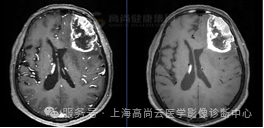

女性,68 岁,2 周前出现语言不流利,行头颅 MRI 平扫示左顶叶占位,考虑肿瘤性病变,建议增强检查。否认药物过敏史。

左顶叶可见团块状异常信号灶,大小约 38 mm×30 mm×35 mm,形态不规则,T1WI 呈稍低信号,T2WI 及 FLAIR 呈稍高信号,DWI 高信号,相应区域 ADC 呈稍低信号,ADC 值约 0.829×10-3 mm2/s,病灶内多发不规则囊变,相应区域 T1WI、DWI 呈低信号,FLAIR 呈低信号,T2WI 呈高信号,病灶局部 MRS 显示 Cho 峰增高,NAA 峰降低,Cho/NAA 比值约 3.45,增强时实性部分呈不规则、不均匀环形强化,部分呈延迟强化,相应区域灌注扫描显示 CBF 增高,邻近脑膜增厚、强化,周围可见大片水肿信号影环绕,邻近脑沟裂、脑池变浅,左侧脑室后角受压推移。

高级别胶质瘤(4 级)